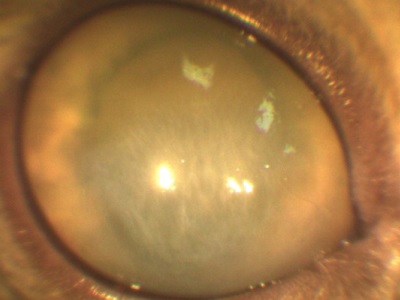

Opacifierea cristalinului (cataractă) este adesea interpretată ca un „spin“. Se sigilează nucleul de lentile, de asemenea, pare tulbure.

Cataracta poate avea loc din motive genetice (cea mai comună cauză), ca urmare a diabetului zaharat, penetrante leziuni corneene, radiații ionizante, și așa mai departe. În funcție de gradul de maturitate a algoritmului de acțiune a cataractei selectat. Cel mai eficient mod de a trata cataracta - o intervenție chirurgicală. Distrugerea substanței opace transportate, eliminarea ei și implantarea lentilelor speciale.

Pentru a distinge cataractă și etanșează miezul necesar să se efectueze examinarea ochilor: biomicroscopie, oftalmoscopie, etc. Pentru a face acest lucru, prezența echipamentului oftalmic este necesar.!